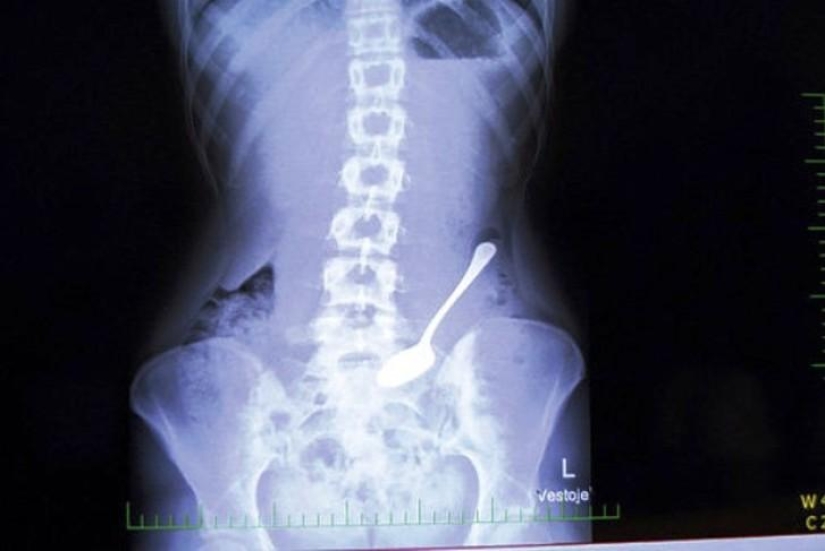

1. Cuchara.